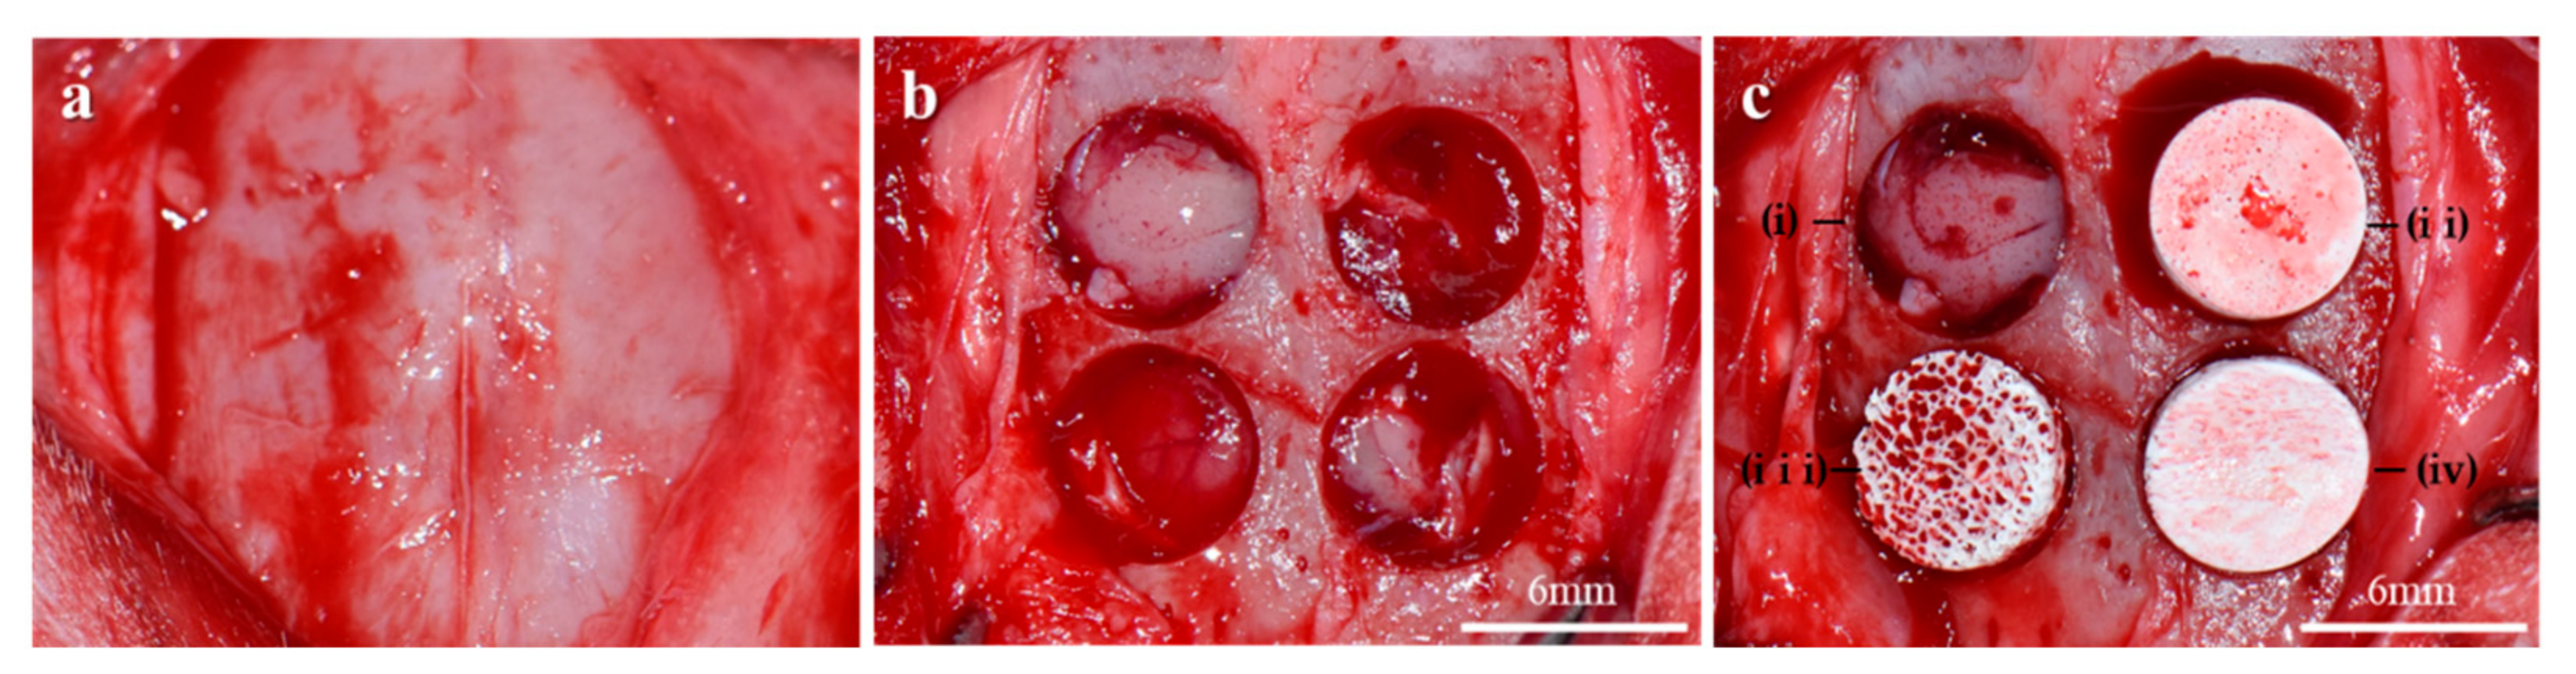

2.2.1. Clinical Findings

4.3.1. Animals and Surgical Procedures